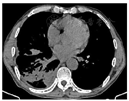

初步诊断:右下肺脓肿,右侧包裹性胸腔积液,支气管哮喘。给予头孢哌酮舒巴坦(3 g,1次/12h)静脉滴注抗感染,同时予吸氧、解痉平喘、止咳祛痰、补液、营养支持等对症治疗。为除外肿瘤和结核,于11月1日行支气管镜检查,见右肺下叶段支气管黏膜充血肿胀,可见散在黄褐色黏痰;在右肺上叶前段、右肺下叶行支气管肺泡灌洗。肺泡灌洗液涂片:上皮细胞≤10/LP、白细胞≥25/LP,G+杆菌1+,G—杆菌1+,查见少量G—双球菌,结核分枝杆菌复合群阴性,未查见抗酸杆菌和真菌。肺泡灌洗液培养:铜绿假单胞菌,对头孢哌酮舒巴坦敏感。复查红细胞沉降率94 mm/h;血常规:白细胞计数22.41×109/L,中性粒细胞绝对值19.07×109/L,淋巴细胞绝对值0.84×109/L,血红蛋白109 g/L,中性粒细胞百分率85.1%;C反应蛋白360.21 mg/L;降钙素原1.25 ng/ml。患者痰量较前增加,呈腥臭味,血液炎症指标仍高,联用克林霉素(0.6g,1次/8h)静脉滴注以覆盖厌氧菌,并再次送检痰培养,仍呈阴性。完善胸部彩超检查示:左侧胸腔肋膈角探及间距约1.3 cm无回声区,右侧胸腔探及范围约5.8 cm×10.8 cm液性暗区反射,其内可见蜂窝状稍强回声分隔,透声差;另于穿刺点处探及范围约6.6 cm×2.9 cm液性暗区反射,进针深度约2.8 cm;右肺组织内探及多处液性暗区反射,其内透声差,可见絮状低回声漂浮,较大范围约7.9 cm×4.9 cm;提示双侧胸腔积液(右侧包裹性),右肺超声所见考虑肺脓肿。因进针深度不够,床旁胸腔穿刺失败。于11月2日在超声引导下行胸腔穿刺术,胸水常规:深黄色、浑浊胸水,无凝块,白细胞总数45660 ×106/L,单个核细胞25%,多个核细胞75%,红细胞30×109/L,李凡他实验+++;胸水生化:白蛋白29.6 g/L,球蛋白25.6 g/L,总蛋白55.2 g/L,淀粉酶30 U/L,葡萄糖0.31 mmol/L,乳酸脱氢酶2427 U/L,腺苷脱氨酶72 U/L;胸水培养(需氧菌+厌氧菌)阴性。胸水检验结果支持脓胸。胸部增强CT(图4,图5,图6):右肺下叶团块状影,考虑肺脓肿,伴脓胸形成,建议治疗后复查除外肿瘤;双肺下叶散在感染灶,较前加重;右侧胸膜增厚,右侧胸腔积液,部分包裹;纵隔淋巴结肿大。